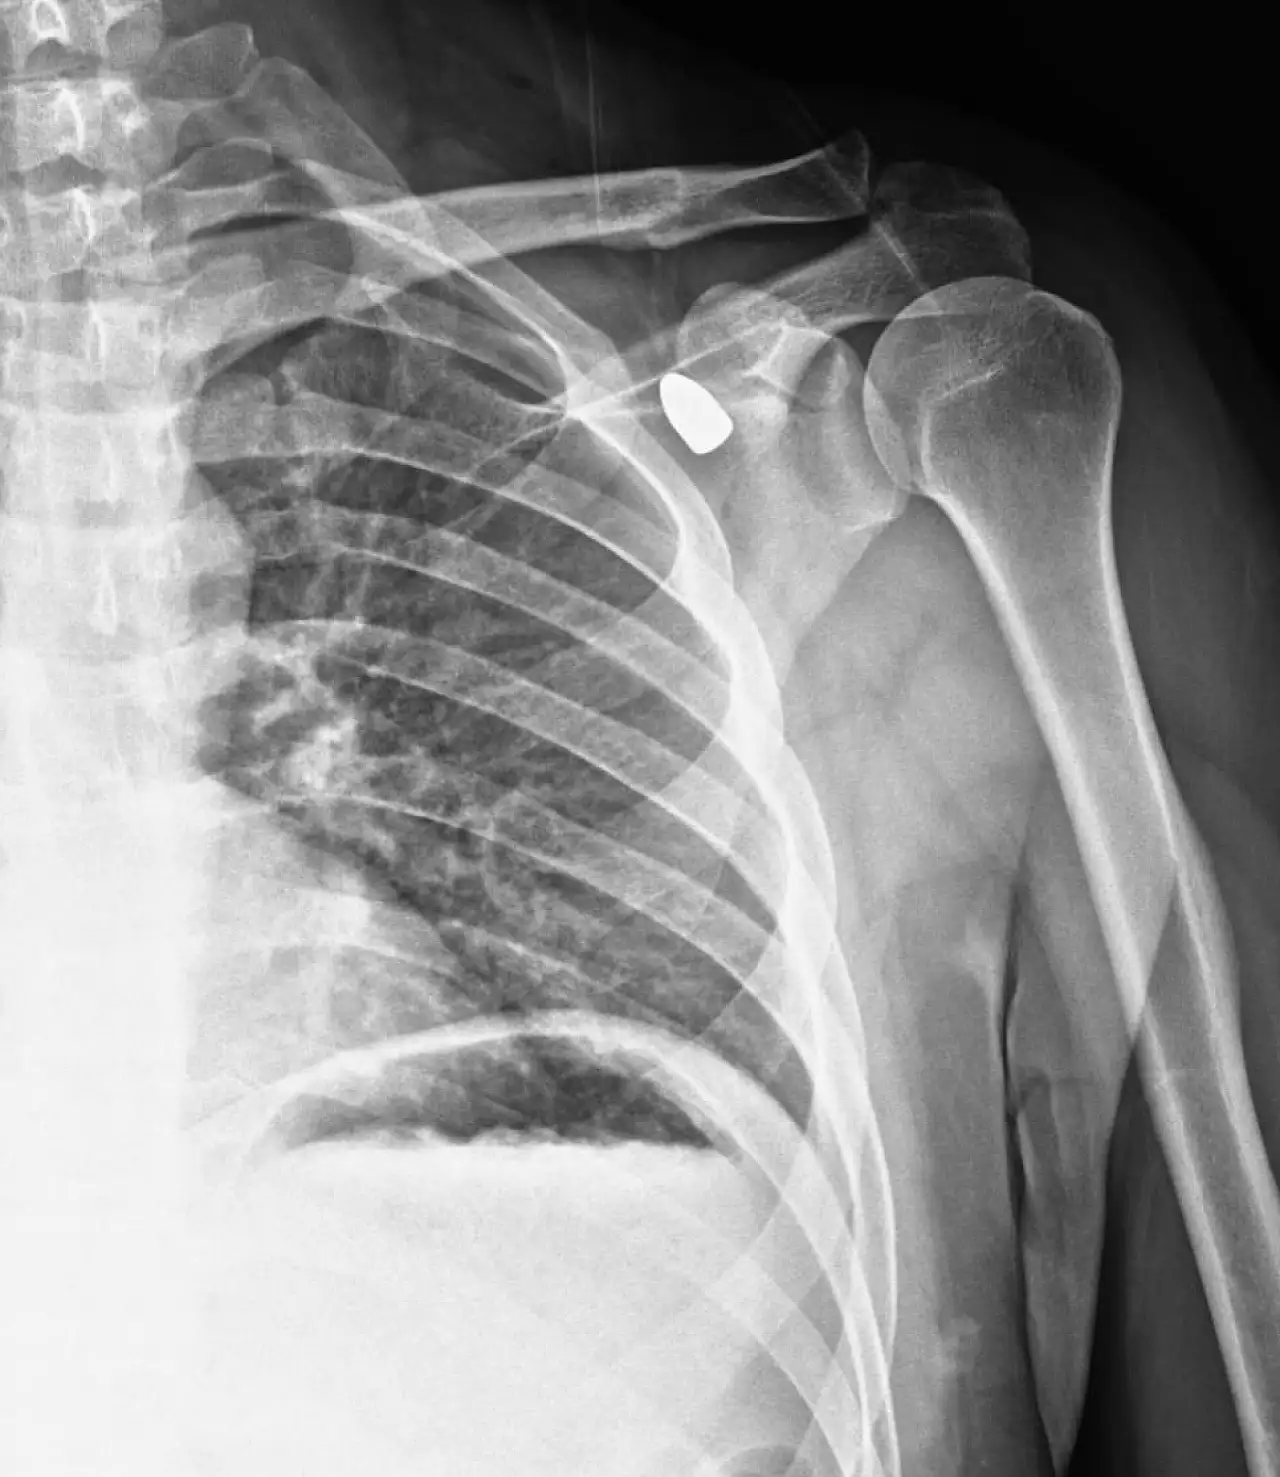

Konya'nın Akşehir ilçesinde altı yıl önce yorgun merminin hedefi olan okul müdürü Celal Şenyiğit, yıllar sonra vücudundaki mermiyle yeniden hastaneye kaldırıldı. Zamanla koltuk altına ilerleyen mermi, başarılı bir operasyonla çıkarıldı.

Konya'nın Akşehir ilçesinde altı yıl önce bir okul müdürünün omzuna isabet eden yorgun mermi tıbbi müdahale sonucu çıkarıldı.

Okul müdürü Celal Şenyiğit, Adsız Mahallesi'ndeki çay ocağında, altı yıl önce omzuna isabet eden yorgun mermiyle yaralandı.

Hareket kaybı riski sebebiyle çıkarılamayan mermi, zamanla Şenyiğit'in koltuk altına ilerledi. Ağrı ve sertlik şikayetiyle Akşehir Devlet Hastanesine başvuran Şenyiğit'in koltuk altındaki kitlenin, omzuna saplanan yorgun mermi olduğu belirlendi.

Mermi, gerçekleştirilen operasyonla çıkarıldı.